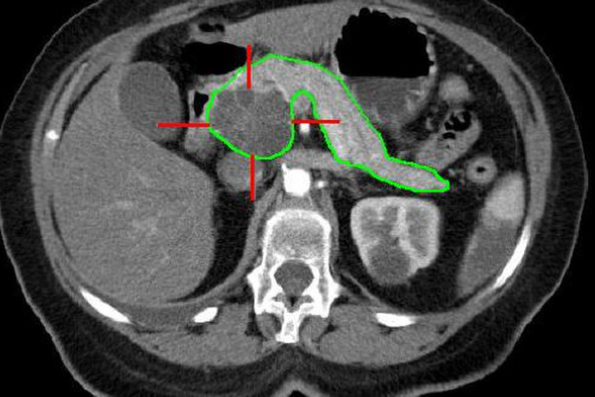

This paper gives the Canadian perspective in approaching incidental findings in the pancreas, including anatomic variants, fatty atrophy, calcifications, ductal ectasia (dilated duct), and incidental cysts. The paper also acknowledges the unique variety of imaging modalities and limited resources.

Pancreatic cysts are very common, and a vast majority of them are developmental or from prior diseases (ie. benign). This is the recommended Canadian approach:

Diverse pseudomasses in the pancrease, including ductal ectasia, pancreatic cysts, anatomic variants, and lipomatosis are explored. Set guidelines are important in properly investigating the etiologies of the patient's illness without subjecting them in further harm.